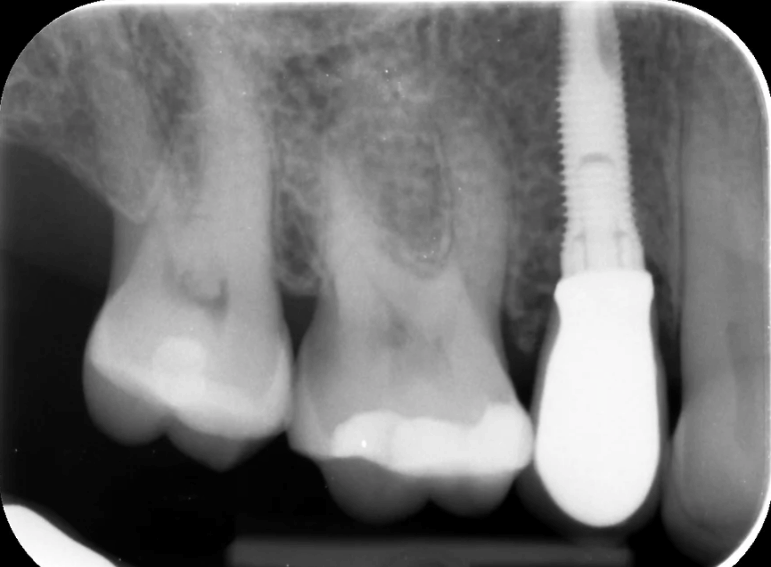

Case 3 – Implants

Removal of a premolar and replacement with an implant.